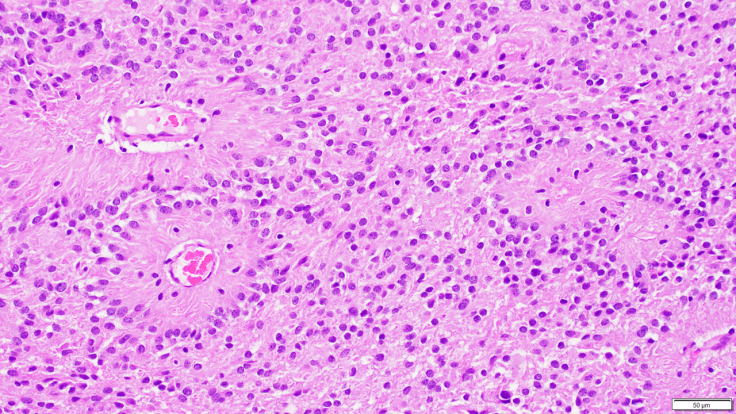

Ependymomas are glial tumors that commonly harbor perivascular pseudo-rosettes, seen here, characterized by radially arranged tumor cells around a blood vessel core. To learn more about these WHO grade 2 tumors, visit Video: Ependymomas explained.for a narrated video.